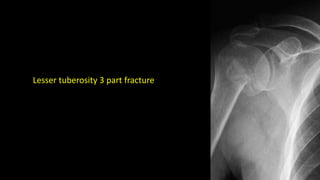

Lesser tuberosity 3 part fracture

Lesser tuberosity 3part fracture